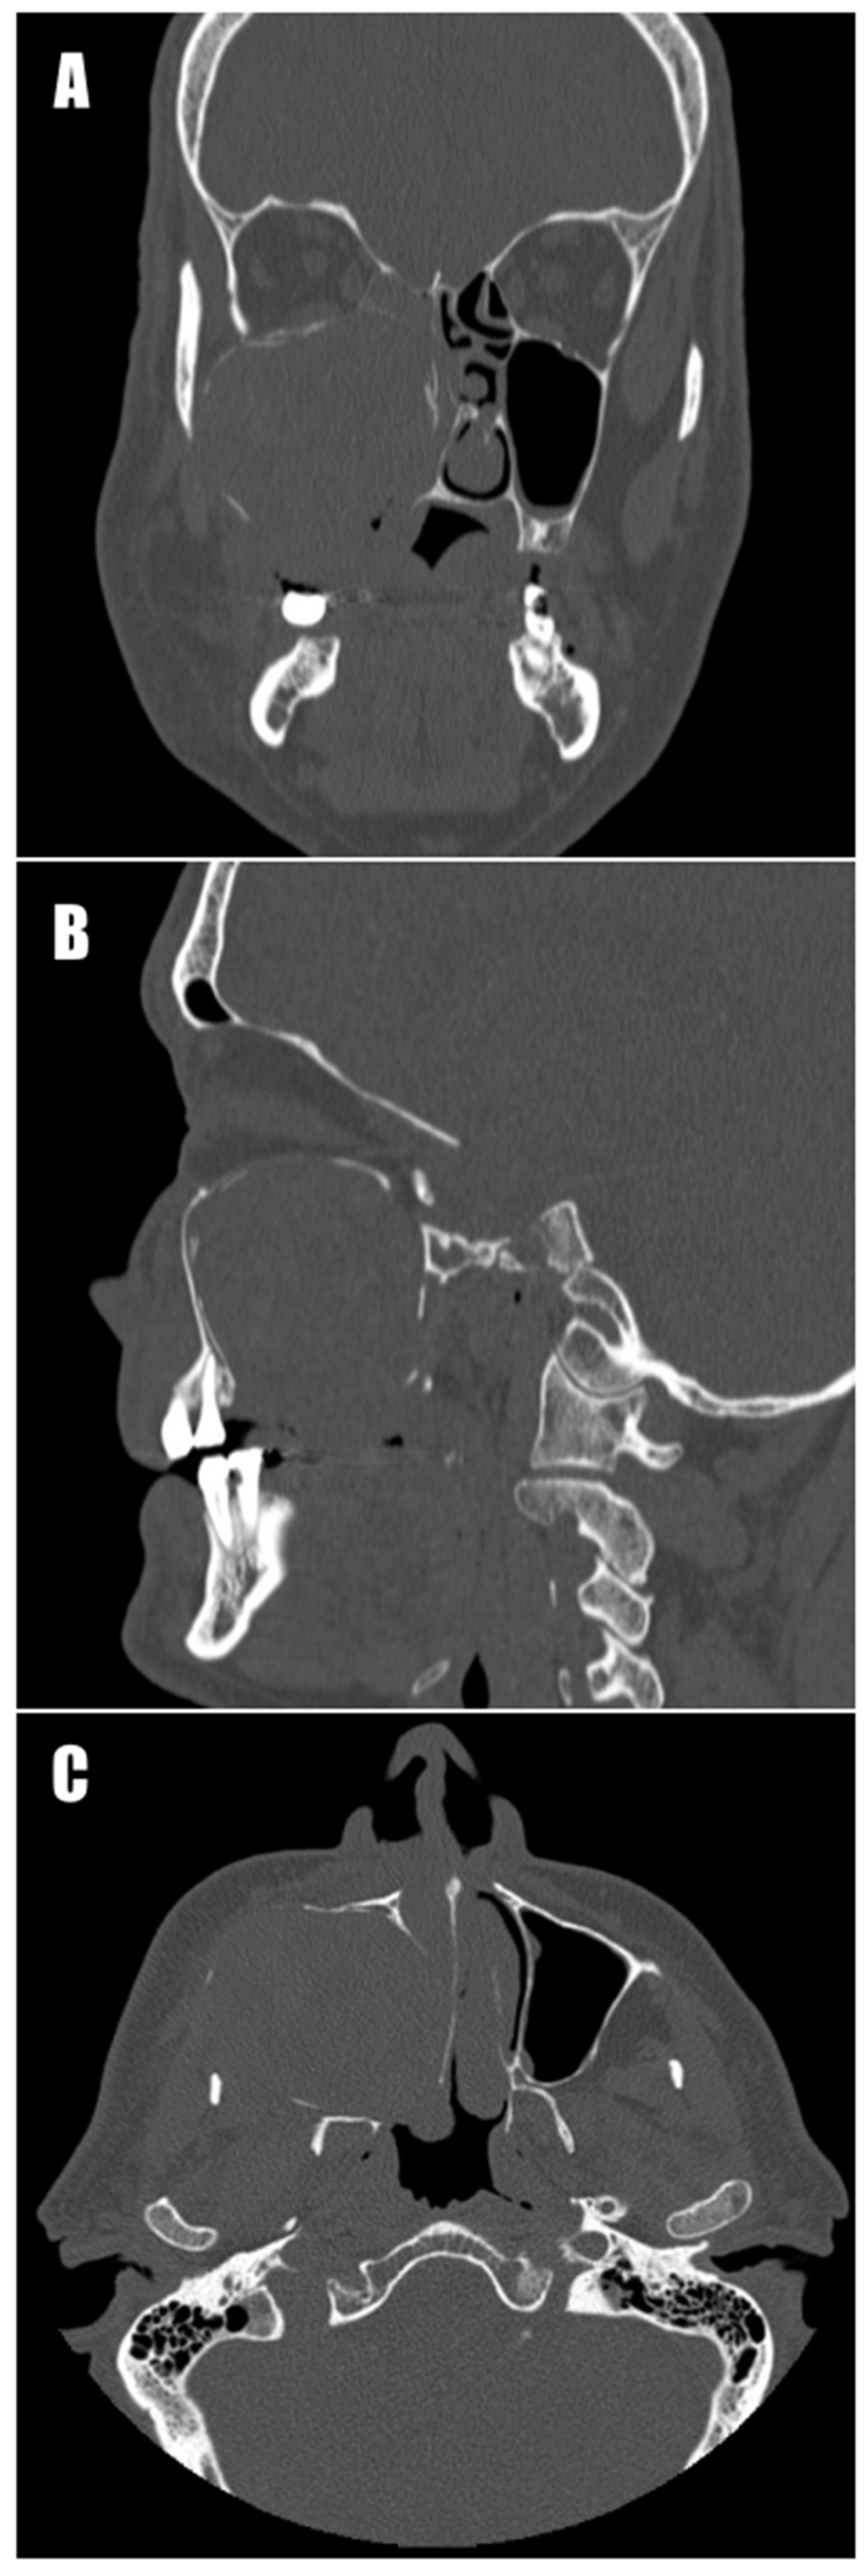

The histological examination revealed fragments of connective tissue stroma, partially stroma covered by non-keratinizing stratified squamous epithelium and, in other regions, glandular epithelium characteristic of the upper respiratory tract. These fragments were associated with extensive hemorrhages and aggregations of nonspecific granulation tissue as well as numerous clusters of blood vessels, some with dilated lumens. Additionally, adjacent bone fragments were present with areas of thickened trabeculae intersected by bands of fibrous connective tissue, among which numerous blood vessels were also visible. Surrounding these vessels were rejuvenated, regenerating trabeculae and fragments of new bone. Chronic inflammation obscured the visualization of typical cystic features during the final histological examination, and hemangioma was suggested for the differential diagnosis. A follow-up computed tomography scan revealed complete removal of the tumor (Figure 4). During further hospitalization, the patient developed secondary anemia, necessitating transfusion of another unit of red blood cell concentrate. Additionally, Clostridium perfringens was isolated from an ulceration on the patient’s left lower leg, requiring antibiotic treatment. This wound healed before the patient was discharged from the unit.

Figure 4. Computed tomography scan after removal of the cyst. (A) Frontal section. (B) Sagittal section. (C) Axial section. There are visible defects in the medial maxillary wall and nasal structures.